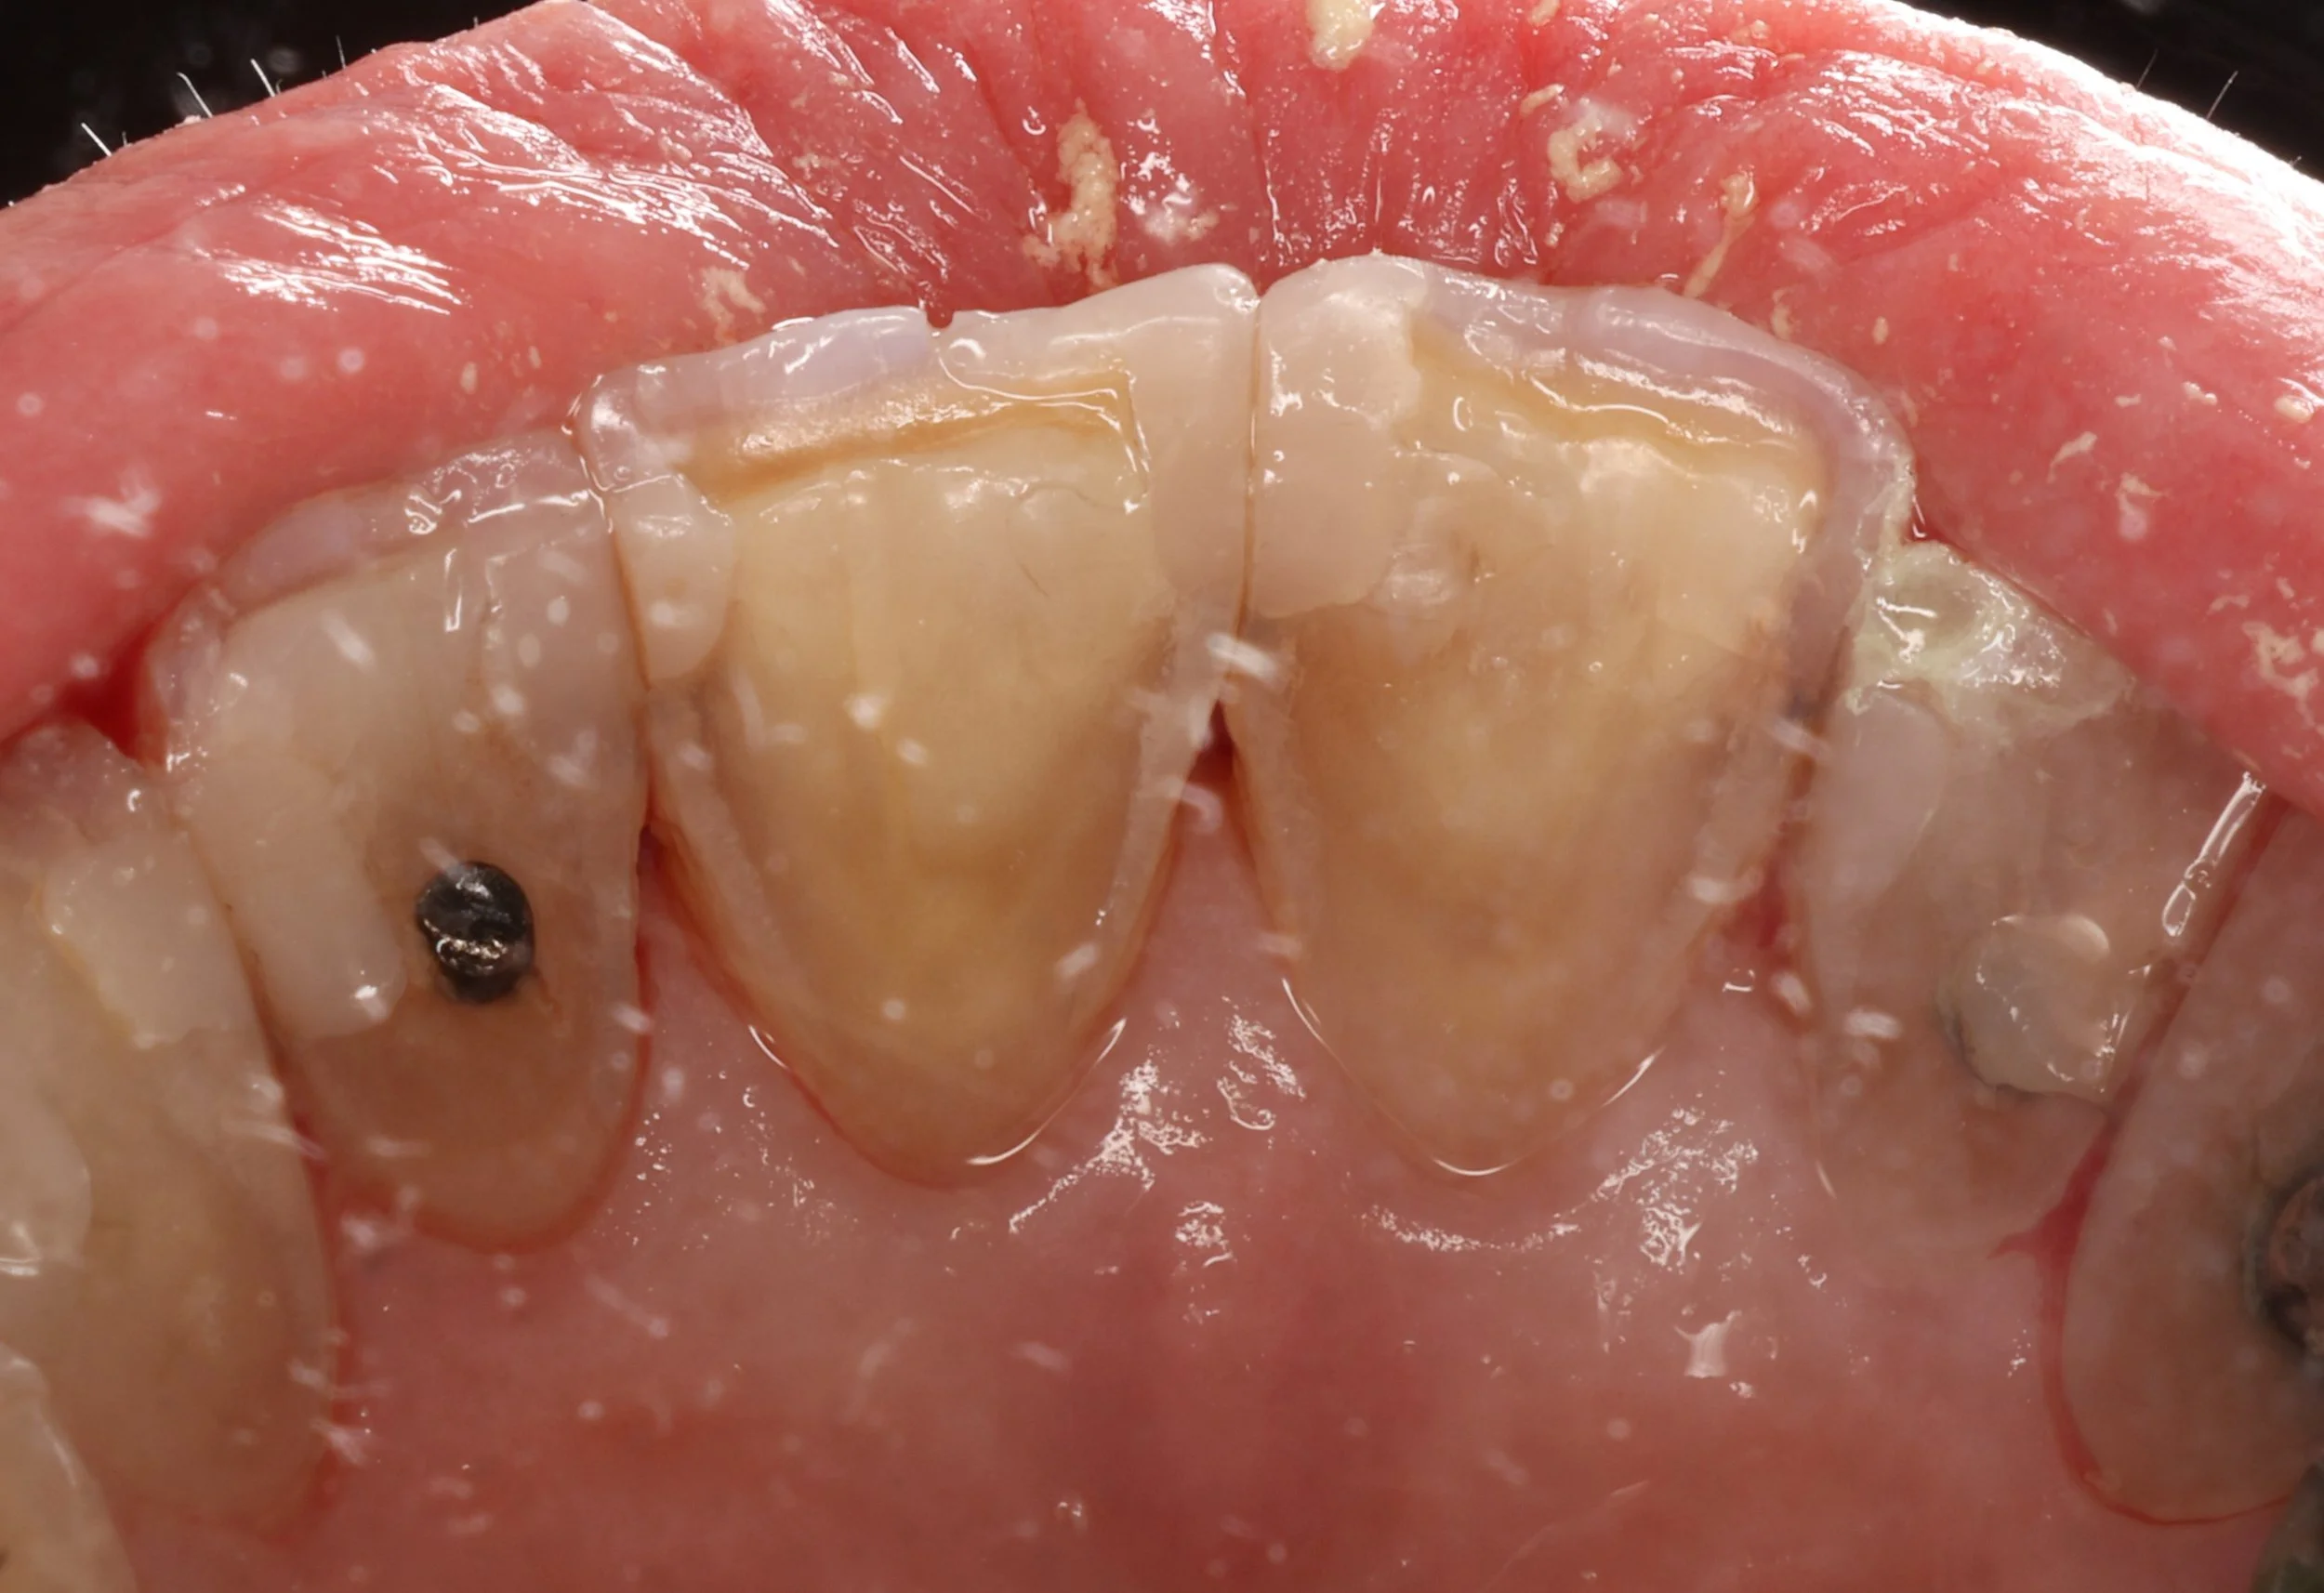

Injection moulding — guided by digitally planned smile design to achieve precise, natural, and minimally invasive results.

Injection moulding — combining digital smile design and biomimetic precision to recreate nature’s beauty with minimal intervention.